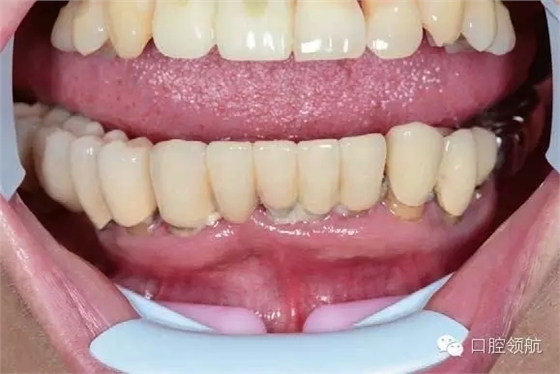

下頜為十?dāng)?shù)年前制作的三組金屬烤瓷橋修復(fù)體。右下4、5、7帶缺失的6;右下3、1及左下1、2帶缺失的右下2;左下3、4、5、8帶缺失的6、7,左下8修復(fù)后牙齒自然脫落,全景片無左下8的影像。幾乎所有的余留牙周圍的骨質(zhì)均吸收到根尖1/3。臨床上三組下頜金屬烤瓷橋均有較大幅度的松動(圖6-7,圖6-8)。

圖6-7 術(shù)前口內(nèi)照片

患者為64歲女性,自述下頜咬合無力,牙齦經(jīng)常出血,有反復(fù)腫脹史,要求拔除后種植修復(fù)。